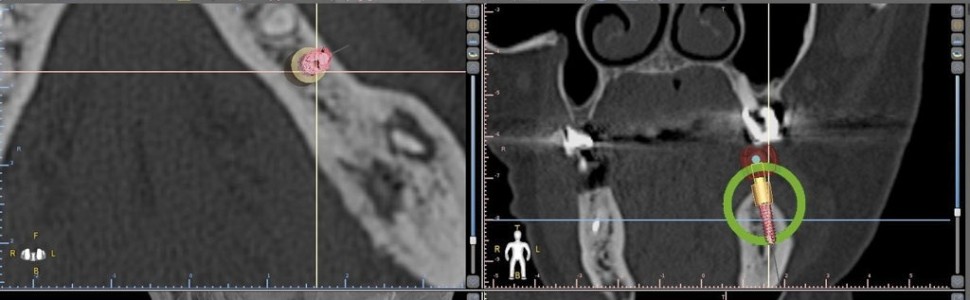

Praca zawiera podstawowe informacje dotyczące stomatologicznych szablonów implantologicznych. Autorzy omawiają rodzaje szablonów, procedurę wykonania, wyniki i powikłania związane z ich użyciem oraz czynniki wpływające na dokładność implantacji z ich zastosowaniem.

The study contains basic information regarding dental implant guides. The authors discuss types of templates, the procedure that is carried out, the results and complications associate with their use, together with the factors influencing the accuracy of implantation with their use.